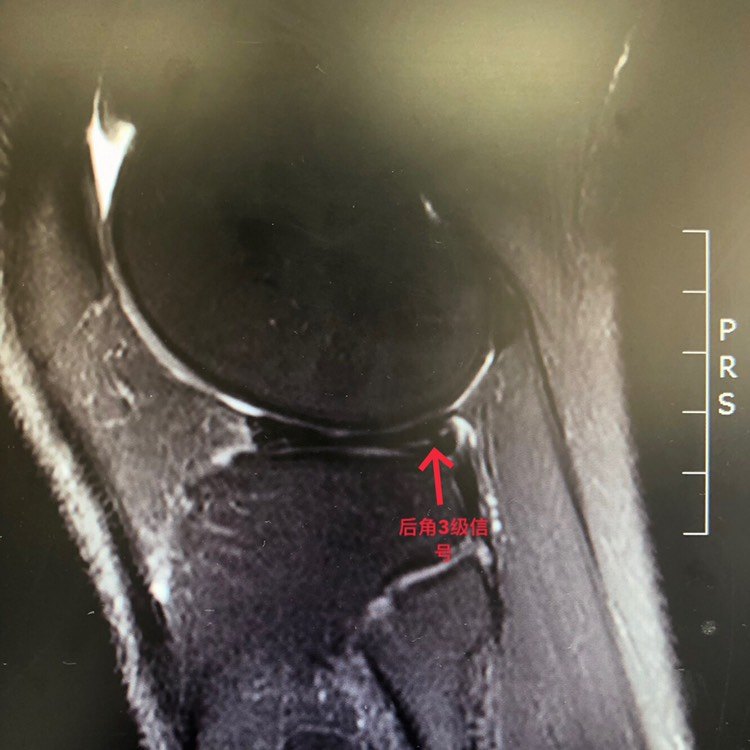

半月板损伤如何分级? - 知乎

上图是mir显示外侧盘状半月板的层裂红箭头所指3,全关节内的技术2,由